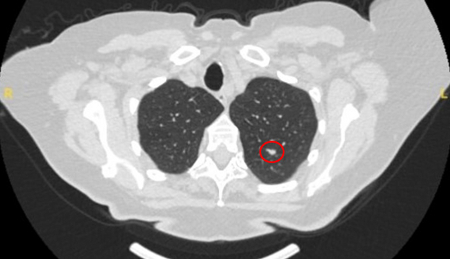

Tomografia computadorizada (TC) mostrando um pequeno nódulo no lobo superior esquerdo com margens lisas, posteriormente considerado uma metástase colorretal solitária na ressecção

Do acervo de Dr. George Tsaknis, MD, PhD, FRCP (Londres), MRQA, MAcadMEd, PGCert; usado com permissão